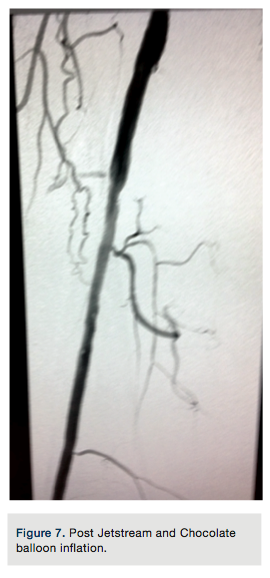

to gain purchase in the distal vessel within the true lumen. Placement was confirmed with a hand injection angiogram into the popliteal artery. There was no evidence of dissection. Routine debulking atherectomy was performed with the Jetstream Navitus 2.4 to 0.4 mm device with blades down (Figure 3) and blades up across the occluded segment (Figures 4-5) over the Spartacore wire. Balloon dilation was then performed with 5.0 x 80 mm and 6.0 x 80 mm Chocolate balloons (Trieme Medical)

(Figure6). There was an excellent angiographic result (Figure 7). The final angiographic image showed a -10% residual stenosis and brisk flow distally, with no dissection or extravasation of contrast. A pullback gradient assessment of femoral and popliteal artery to the proximal right SFA was performed and no gradient found. The Pinnacle Destination sheath was removed and a Perclose (Abbott Vascular) technique was used for left common femoral artery vascular access closure.